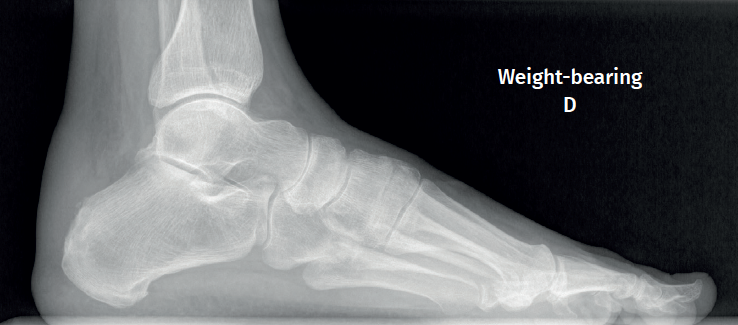

Figure 3. Plain radiography, Sagittal view with weight-bearing. Moderate calcifications in the insertion of the Achilles tendon with intratendinous enthesophyte. Morphological alterations of the posterior tuberosity of the calcaneus.

Plain radiography under loading conditions is the essential initial diagnostic tool(20). It allows us to assess alignments and dysmetria, to measure angles, to determine the morphology of the calcaneus and its posterior tuberosity, to characterise bone exostosis and increments in thickness of the retrocalcaneal soft tissues, and to plan surgical procedures (Figure 3).